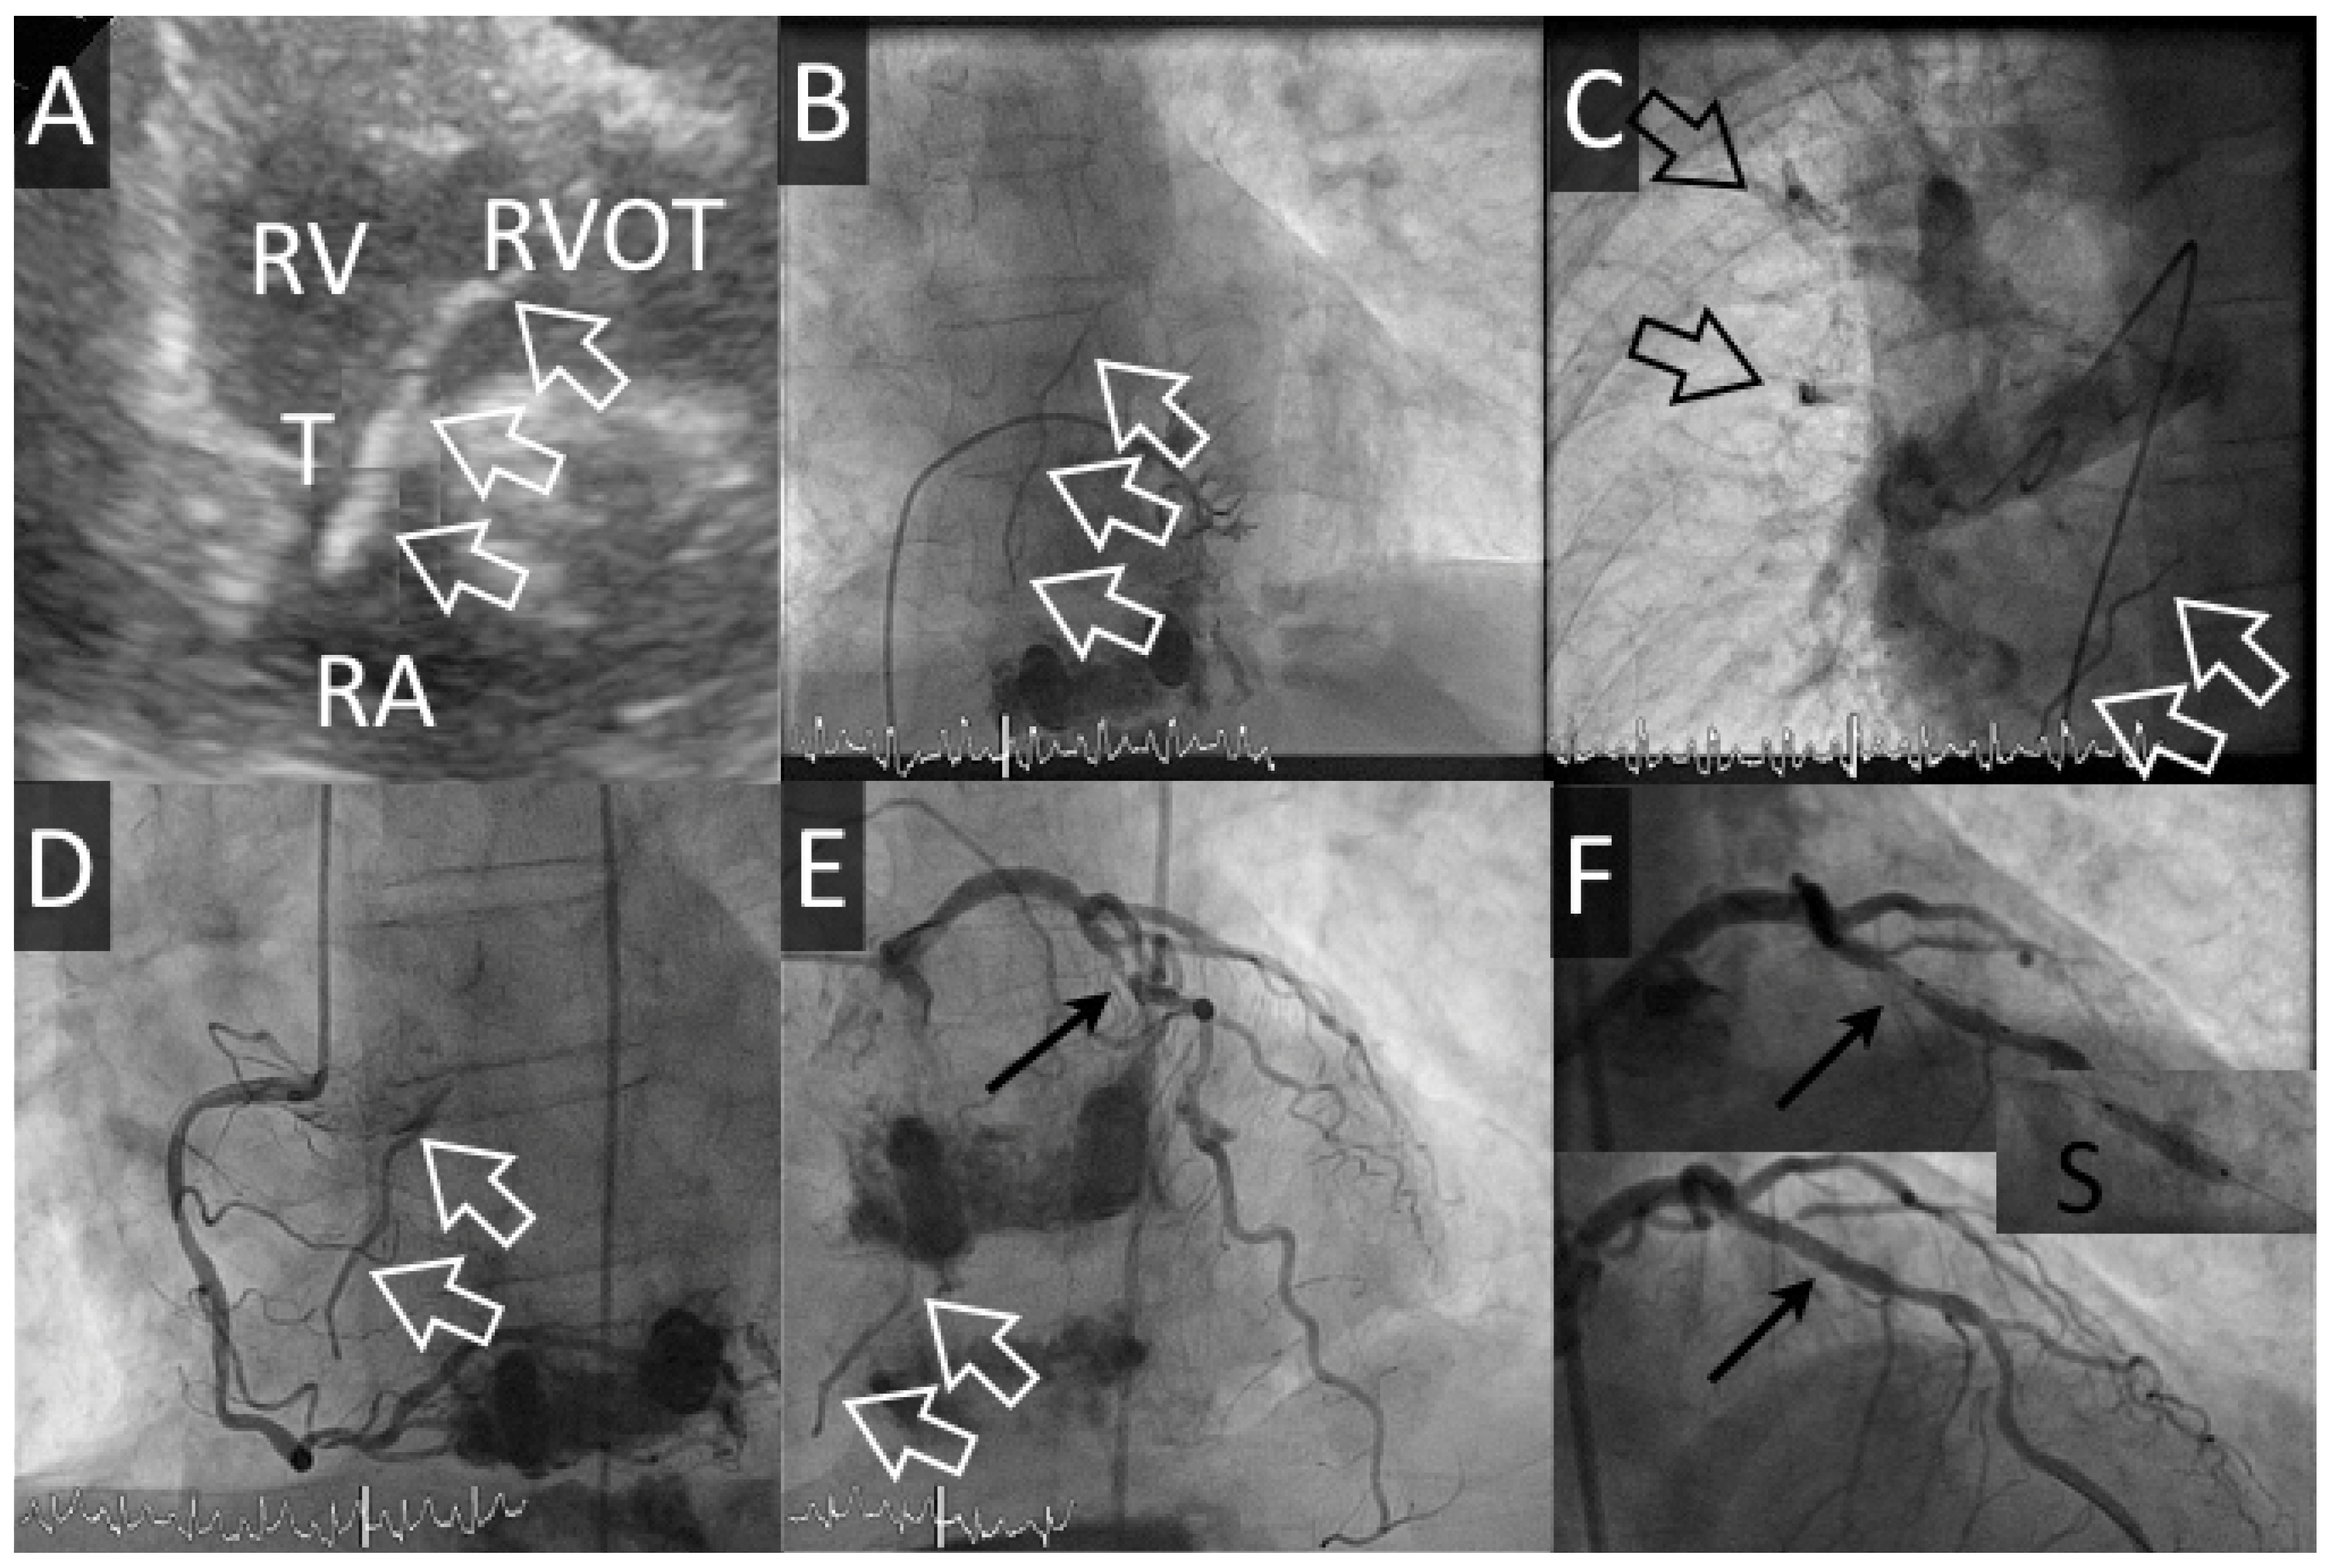

Figure 2. Cas #2. Panel A. Echocardiographie transthoracique avec filament de ciment (flèches blanches creuses) de l’oreillette droite (RA) à la chambre de chasse droite (RVOT) au travers de la valve tricuspide (T). Panel B. Le même filament est visible pendant la dextrographie et des emboles périphériques sont visibles pendant l’artériographie pulmonaire (Panel C). Panel D-F: La coronarographie démontre une sténose serrée de l’artère interventriculaire antérieure (flèche noire), qui est traitée en passant par la mise en place d’un stent actif (S) avec bon résultat final.

Une patiente de 66 ans avec BPCO Gold IV et oxygénothérapie bénéficie d’une troisième cyphoplastie (dernière cyphoplastie de D11 et D12, 2 mois auparavant) de L1 pour des fractures tassements symptomatiques sur ostéoporose. Durant l’intervention, une fuite de ciment est visualisée dans une veine péri-vertébrale gauche mais n’a pas de conséquence hémodynamique. Environ 5 heures après la fin de l’intervention, la patiente rapporte de vives douleurs latéro-thoraciques gauches associées à une exacerbation de sa dyspnée chronique, une désaturation (SatO2 84%), une hypotension artérielle (101/62 mm Hg) et une tachycardie sinusale (à 104 bpm). L’ECG est inchangé et la troponine-hs est à 30 ng/l (14 < zone grise < 50 ng/l). La radiographie du thorax montre des opacités dans les lobes supérieur et para-hilaire droits. Une échocardiographie démontre de plus un filament au travers de la valve tricuspide. Une coronarographie est effectuée en raison des douleurs thoraciques répondant aux nitrés et non explicables par les emboles de ciment intra-pulmonaires. Cet examen confirme l’embolisation pulmonaire et la présence d’un embole figé en transit au travers de la valve tricuspide. Le cathétérisme cardiaque droit montre une discrète hypertension artérielle pulmonaire (35 mm Hg, probablement chronique sur la BPCO connue). En l’absence de répercussion hémodynamique, un traitement conservateur est proposé et une sténose serrée de l’artère interventriculaire antérieure découverte fortuitement est traitée (2,75/12 mm—Xience Alpine, Abbott Vasc) après discussion avec la patiente. Une triple thérapie par aspirine, clopidogrel et anticoagulation orale est initiée pour un mois, suivi de 5 mois de double antiaggrégation plaquettaire. L’évolution échocardiographique et clinique est simple depuis lors.